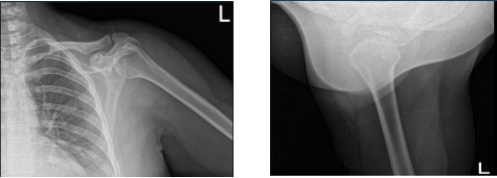

Xray were reviewed and discussed that his left shoulder showed normal radiographs. Advised patient to take MRI for us to see the reason behind and found out partial thickness tear of the subscapularis tendon though there is no high-grade partial or full thickness rotator cuff tear. Presence of supraspinatus and infraspinatus tendinosis.

Left Shoulder X-ray